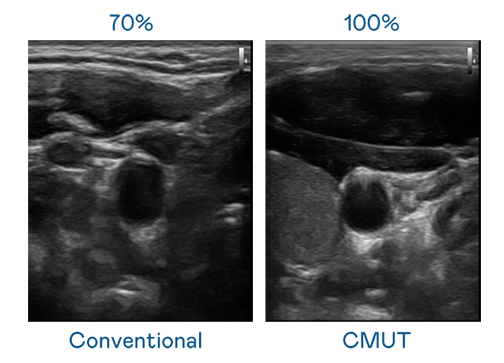

CMUT 技术是一种用电容式微机电元件来产生超音波讯号的技术。与传统 PZT 压电式技术相比,CMUT 频宽增加 30%,更宽频的超音波讯号让影像解析度大幅提升,是实现高影像品质医疗超音波扫描、促进精准医疗发展的关键技术。

大频宽带来超清晰影像

超音波影像的解析度高低,首先取决于探头能发出的讯号频宽。拉斯维加斯5357 CMUT 可提供高清晰的超音波讯号,提供高频宽、高灵敏度、影像纹理细节更高的超音波影像,协助医护人员缩短影像判读时间及利用精准的医疗影像进行诊断。